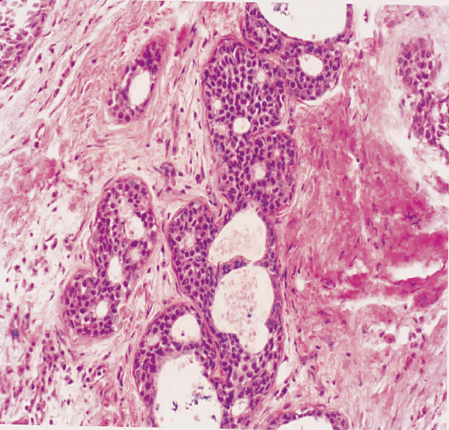

2.增生性纤维囊性变

除了囊肿形成和间质纤维增生外,增生性纤维囊性变往往伴有末梢导管和腺泡上皮的增生。上皮增生可使层次增多,并形成乳头突入囊内,乳头顶部相互吻合,构成筛状结构。囊肿伴有上皮增生,尤其是有上皮异型增生时,有演化为乳腺癌的可能,应视为癌前病变。

非增生性纤维囊性变无继发浸润性癌的危险性,旺炽型增生性纤维囊性变癌变的危险度增加1.5-2倍,导管和小叶的非典型性增生演变为浸润性癌机会增加5倍,而导管和小叶的原位癌进一步发展为浸润性癌的可能性则增加至10倍。说明乳腺纤维囊性变无论是临床、放射线影象,还是病理变化均与乳腺癌有某些相似之处,和癌的发生的确有一定关系,但是否发展为乳腺癌主要取决于导管和腺泡上皮增生的程度和有无非典型性增生。